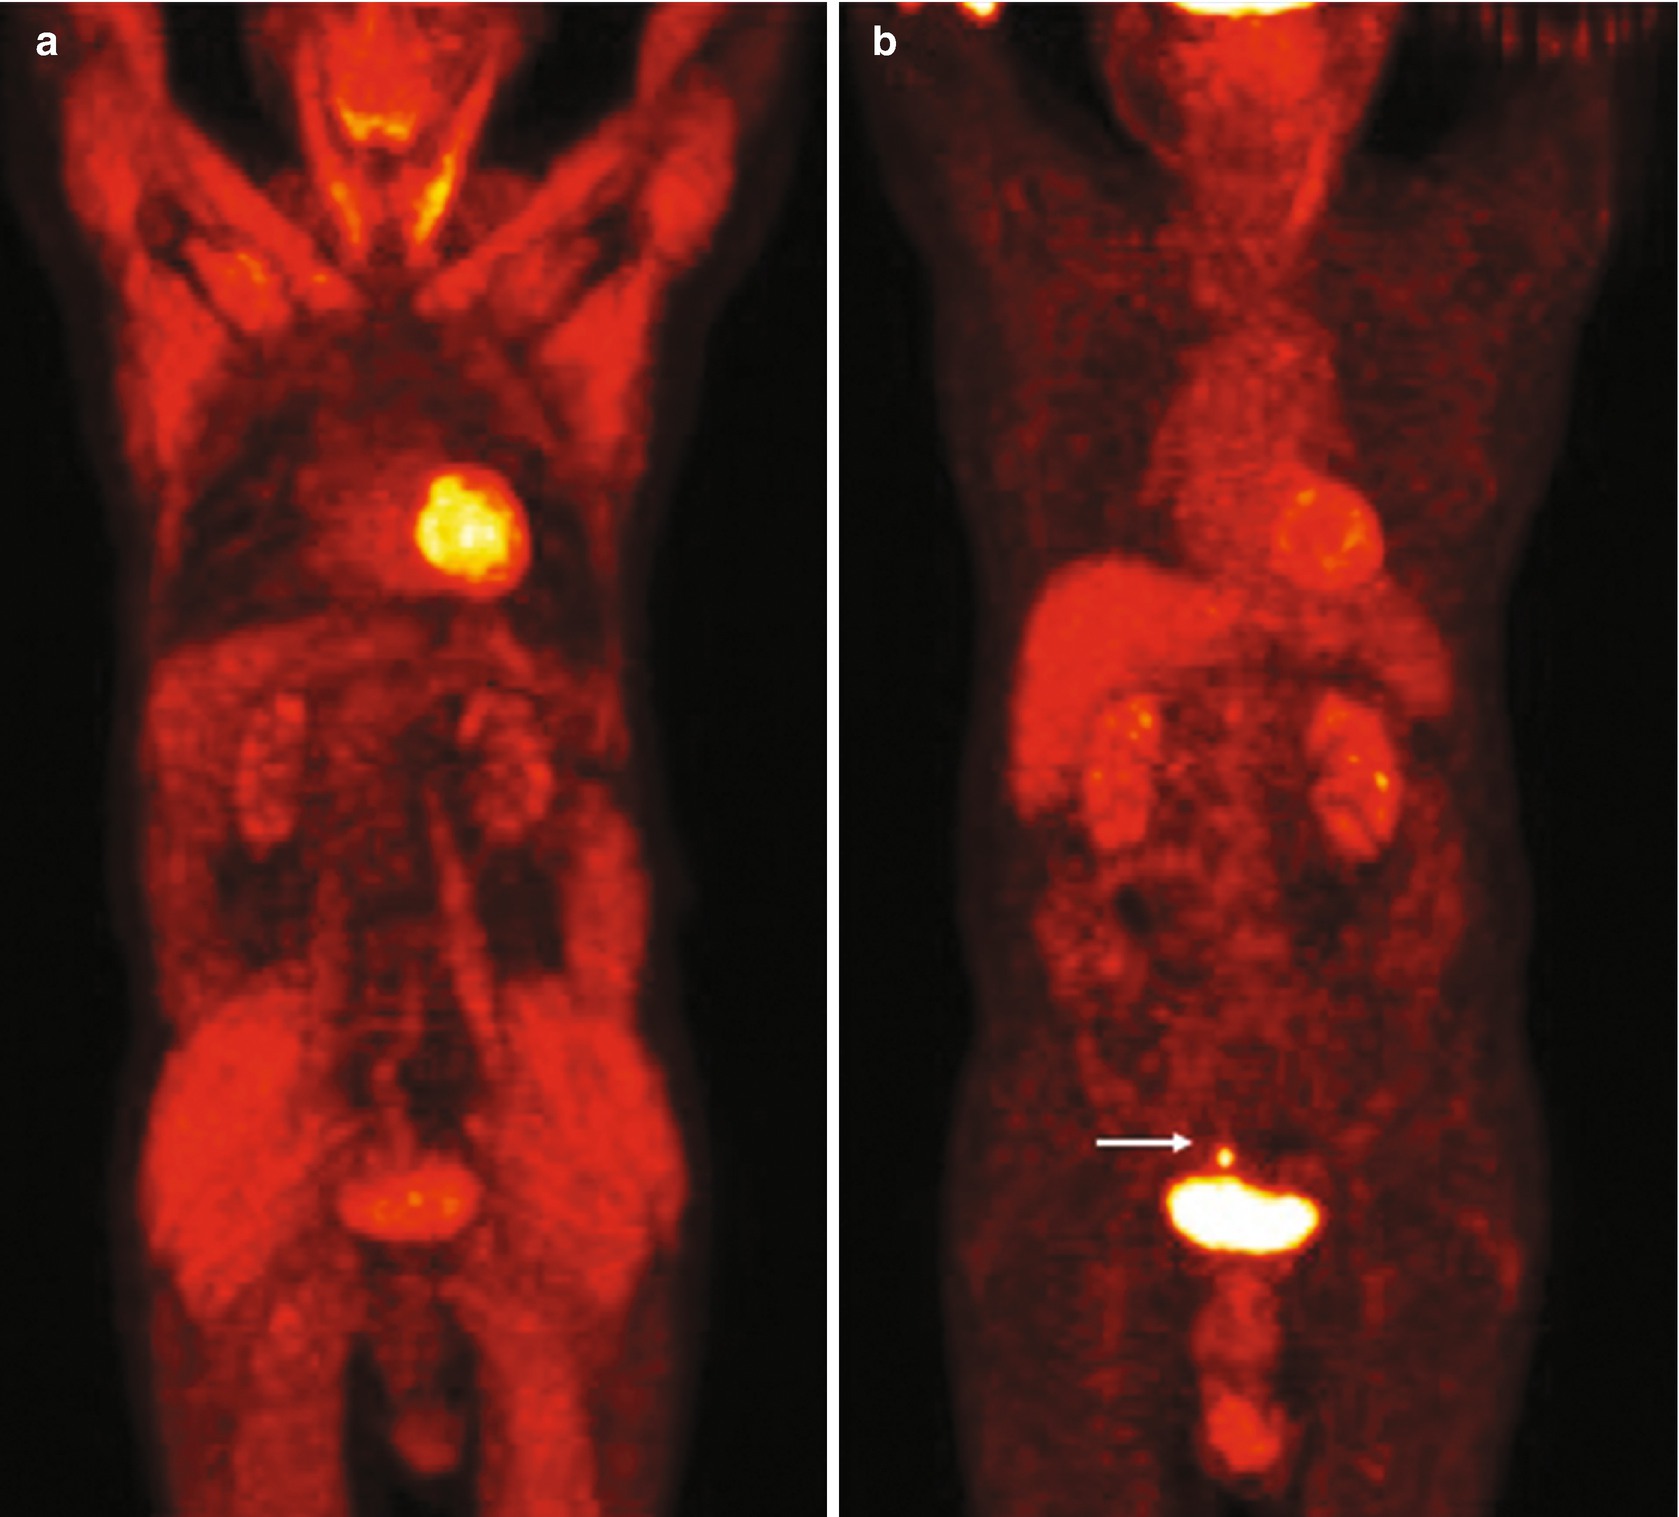

- Role Of Imaging In Early Phase Trials Sciencedirect , In Vivo Molecular Imaging With Pet Can Be Regarded As A True Classifier With Regard To Tumor Cell Characteristics As It Can Provide A Global Assessment Of A Given Tumor Via Characterization Of The Subpopulations Of The Cell (Table 1 ).

Through pet, tumor heterogeneity has clearly been observed in.